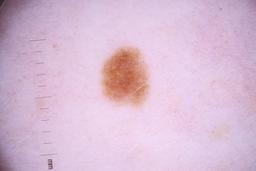

ISIC_4077341

- Challenge 2020: Training

- IP_1969685 IL_9238622

Clinical

| Field | Value |

|---|---|

| acquisition_day | 1 |

| age_approx | 50 |

| anatom_site_1 | Trunk |

| anatom_site_2 | Anterior trunk |

| concomitant_biopsy | False |

| dermoscopic_type | contact non-polarized |

| diagnosis_1 | Benign |

| diagnosis_confirm_type | serial imaging showing no change |

| family_hx_mm | False |

| image_type | dermoscopic |

| lesion_id | IL_9238622 |

| patient_id | IP_1969685 |

| personal_hx_mm | True |

| sex | male |